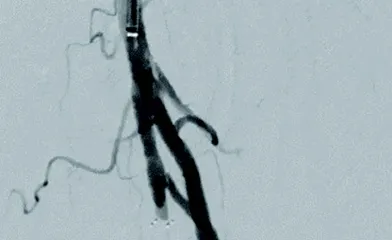

ケースレポート実際の臨床応用を通じて、製品への理解をさらに深めてください。 製品に関連するケースレポートをご覧ください並び替え昇順降順並び替え 昇順降順ポートフォリオ大動脈領域末梢血管領域ポートフォリオ 大動脈領域末梢血管領域関連製品ゴア® TAG® コンフォーマブル 胸部大動脈ステントグラフト アクティブコントロールシステムゴア® エクスクルーダー® IBEゴア® エクスクルーダー® コンフォーマブル AAAステントグラフト アクティブコントロールシステムゴア® バイアバーン® VBX バルーン拡張型ステントグラフト ゴア® バイアバーン® ステントグラフト関連製品 ゴア® TAG® コンフォーマブル 胸部大動脈ステントグラフト アクティブコントロールシステムゴア® エクスクルーダー® IBEゴア® エクスクルーダー® コンフォーマブル AAAステントグラフト アクティブコントロールシステムゴア® バイアバーン® VBX バルーン拡張型ステントグラフト ゴア® バイアバーン® ステントグラフト治療領域末期腎不全末梢血管疾患胸部大動脈疾患腹部大動脈瘤血管損傷治療領域 末期腎不全末梢血管疾患胸部大動脈疾患腹部大動脈瘤血管損傷 34 結果 Image 6 Fr 対応ゴア® バイアバーン® VBXバルーン拡張型ステントグラフトを用いた橈骨動脈アプローチによる腸骨動脈 EVTの一例 さらに詳しくImage AVGの人工血管延長術後に生じた再流出路狭窄症例に対してゴア® バイアバーン® ステントグラフトを挿入した一例 さらに詳しくImage DESによる左浅大腿動脈の慢性閉塞の治療後、コロナ禍の受診中断でステント内閉塞となり再来された一例 さらに詳しくImage SFAの長区域閉塞病変にゴア® バイアバーン® ステントグラフトを留置し、3年フォローした一例 さらに詳しくImage SFA入口部からの長区間超高度石灰化閉塞病変に対して外科的内膜摘除術との併用でゴア®バイアバーン® ステントグラフトを留置し、6か月フォローした一例 さらに詳しくImage SFA起始部のランディングに悩むCTO病変に対しゴア® バイアバーン® ステントグラフトを用いてEVTを完遂し、2年経過を観察した一例 さらに詳しくImage Shaggy Aortaを合併した遠位弓部大動脈瘤に対するTEVAR さらに詳しくImage ケースレポート:ゴア® TAG® コンフォーマブル 胸部大動脈ステントグラフト アクティブコントロールシステム さらに詳しくImage ケースレポート:ゴア® エクスクルーダー® IBE さらに詳しくImage ケースレポート:ゴア® バイアバーン® VBX バルーン拡張型ステントグラフト さらに詳しくImage ケースレポート:ゴア® バイアバーン® ステントグラフト さらに詳しくImage ケースレポート:外傷性胸部大動脈損傷に対するゴア® TAG® コンフォーマブル 胸部大動脈ステントグラフト アクティブコントロールシステムの有用性 さらに詳しくImage ゴア® TAG® コンフォーマブル 胸部大動脈ステントグラフト アクティブコントロールシステムの特徴および有用性 さらに詳しくImage ゴア® バイアバーン® ステントグラフトの使い所 –長期開存したISO症例– さらに詳しくImage ゴア® バイアバーン® ステントグラフトを人工血管内シャント静脈側吻合部狭窄のリコイルに対して用いた症例 さらに詳しく さらに表示 トップ